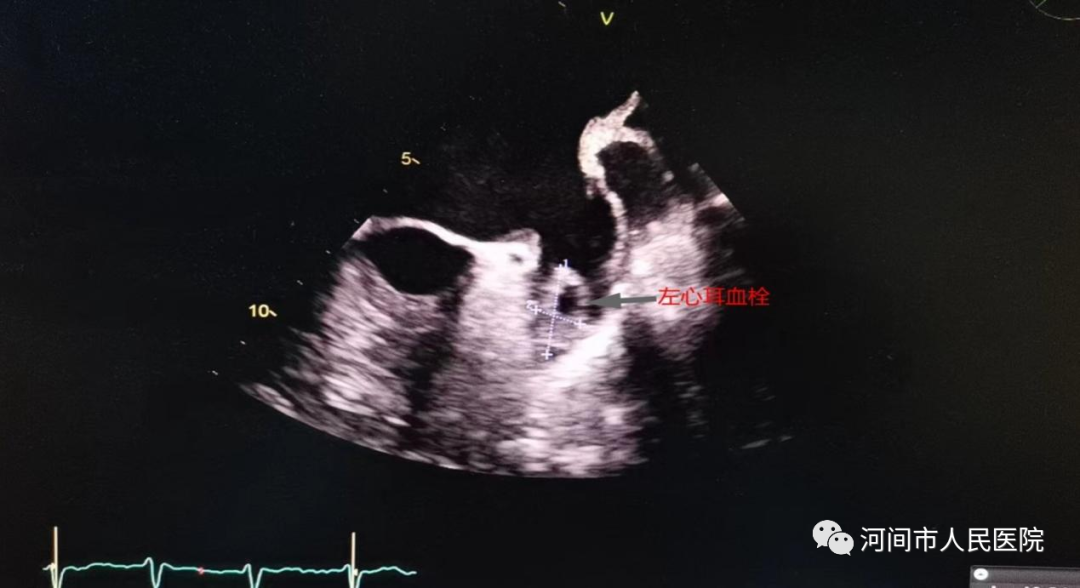

經食管超聲心動圖(TEE)是把超聲探頭放到食管內(nei) ,由於(yu) 探頭更貼近心髒,不像經胸超聲心動圖那樣受胸壁和肺氣影響,圖像顯示的更清晰,特別是對左心耳等經胸超聲不能看到的結構也能清晰顯示。

2、懷疑左心耳和左房的血栓的患者,特別是房顫患者。